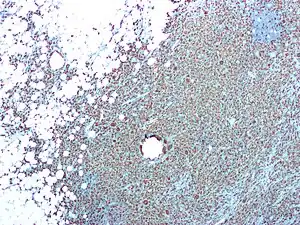

Foreign-body giant cells form when a subject is exposed to a foreign substance. Exogenous substances can include talc or sutures. As with other types of giant cells, epithelioid macrophages fusing together causes these giant cells to form and grow.[13] In this form of giant cell, the nuclei are arranged in an overlapping manner. This giant cell is often found in tissue because of medical devices, prostheses, and biomaterials.